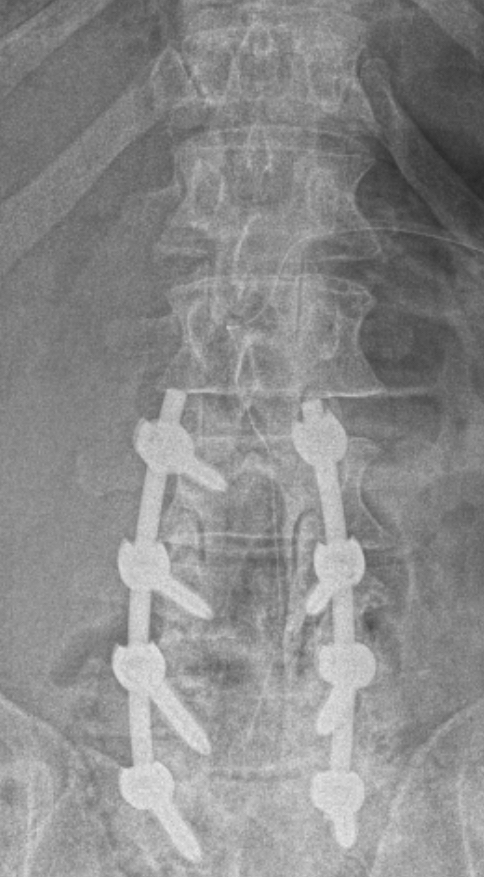

Researchers were using a new robot for Bledsoe’s case that read MRI bone densities to determine the best location for the eight screws that were to be inserted into his vertebrae. Thus guaranteeing the spinal structural support that Bledsoe had been lacking.